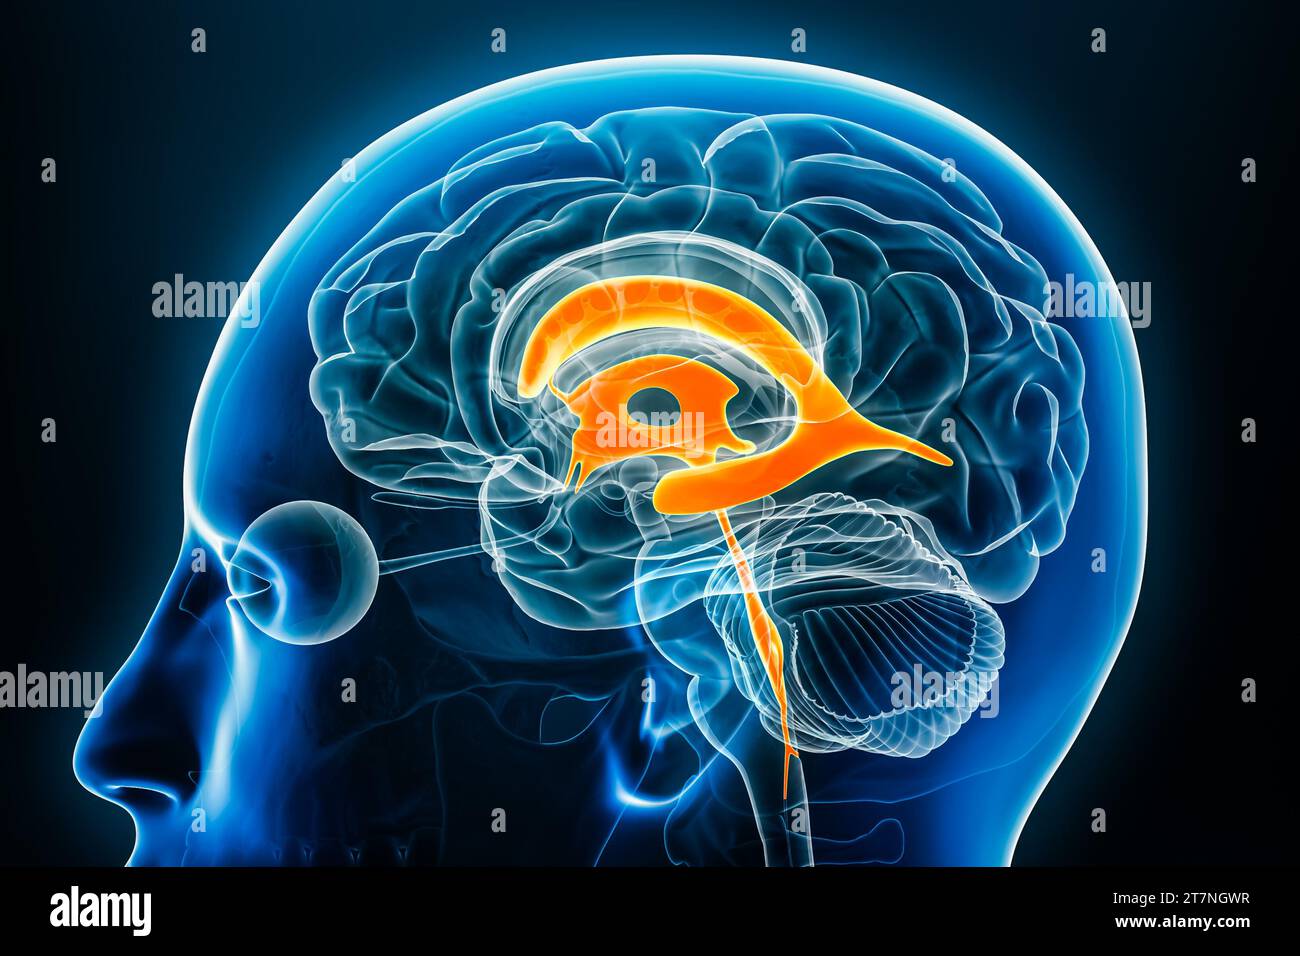

RF2T7NGWH–Ventrikel und zerebrales Aquädukt laterale Röntgenansicht 3D-Rendering-Illustration. Menschliches Gehirn und Ventrikelsystem Anatomie, Medizin, Gesundheitswesen, Scienc

RF2T7NGWK–Ventrikel und zerebraler Aquädukt lateral in Farben Röntgenbild-3D-Rendering-Illustration. Menschliches Gehirn und Ventrikelsystem Anatomie, medizinisch, gesund

RF2T7NGWR–Ventrikel und Hirn-Aquädukt-Röntgenprofil Nahansicht 3D-Rendering-Illustration mit Körperkonturen. Anatomie des menschlichen Gehirns und des Ventrikelsystems,

RM2AWF8JC–Die Anatomie des Nervensystems, vom Standpunkt der Entwicklung und Funktion. -Ant. HornCentra, Teil Latcral vnnInf. Horn Q virale Pari Ant. Horn. Ventrikel Ventrikel Ventrikel Ventrikel Ventrikel Ventrikel Ventrikel Ventrikel Ventrikel Ventrikel Ventrikel Ventrikel Ventrikel Ventrikel Ventrikel Ventrikel Ventrikel Ventrikel Ventrikel Ventrikel ^^ 176.-Zwei Ansichten der Hirnventrikel des Menschen: A, Dorsale Ansicht; B, laterale Ansicht. Das Vorderhorn oder Cornu anterius ist der Teil, der rostral zum interventrikulären Foramen liegt. Seine Dach- und Rostrallgrenze wird von Thecorpus callosum gebildet. Sein mediales

RF2T7NGWW–Ventrikel und zerebraler Aquädukt in Farben Röntgenprofil Nahansicht 3D-Rendering-Illustration. Anatomie des menschlichen Gehirns und des Ventrikelsystems, medizinisch,

RM2AWFNN9–Menschliche Anatomie, einschließlich Struktur und Entwicklung und praktische Überlegungen d in einem sagittalen mesialen Abschnitt (Abb. 910) wird jede dieser Teilungen als mit einem Teil des Systems der Kommunikation von Räumen verwandt angesehen, die als die dritten Ventrikel des Lateralands, der Aquädukt von Sylvius und der vierte Ventrikel die oben genannten Gehirnhemisphären ausdehnen. Durch den Hirnstamm und unter dem Kleinhirn bis zum zentralen Kanal des Rückenmarks. Da die lateralen Ventrikel zwei innumerieren, ist die Theirstellung im Zusammenhang mit den Gehirnhemisphären, in denen sie liegen, lateral zum m